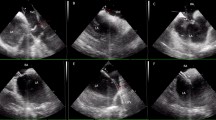

The assembly of sheath, dilator, and flexible RF powered guidewire was pulled down with clockwise rotation towards a 5 o’clock position under fluoroscopic and TOE guidance to engage the middle part of the fossa ovalis (Figs. 2 & 3). Then the radio-opaque distal of Versacross wire was positioned and supported at the edge of the dilator to ensure a perpendicular contact with the interatrial septum. Once proper positioning and tenting of the septum was confirmed with TOE, RF energy was delivered at a fixed frequency in a range of 450 to 480 kHz in a monopolar mode for a one second pulse resulting in the perforation of the septum with minimal pressure applied (Figs. 2 & 3). The guidewire is then advanced into the left atrium where it resumes its pigtail configuration, confirming LA access on TOE, and subsequently supporting progression of the dilator and Faradrive sheath across the septum. The TOE probe was removed following confirmation of LA access post TSP in all cases.

Advancement of the radiofrequency Pigtail wire into the left atrium. Transesophageal views: (A) Radiofrequency wire reshaping to its pigtail form inside the left atrium. (B) Catheter sheath crossing through the septum and into the left atrium. (C) Catheter sheath in the left atrium with the dilator and radiofrequency wire withdrawn.